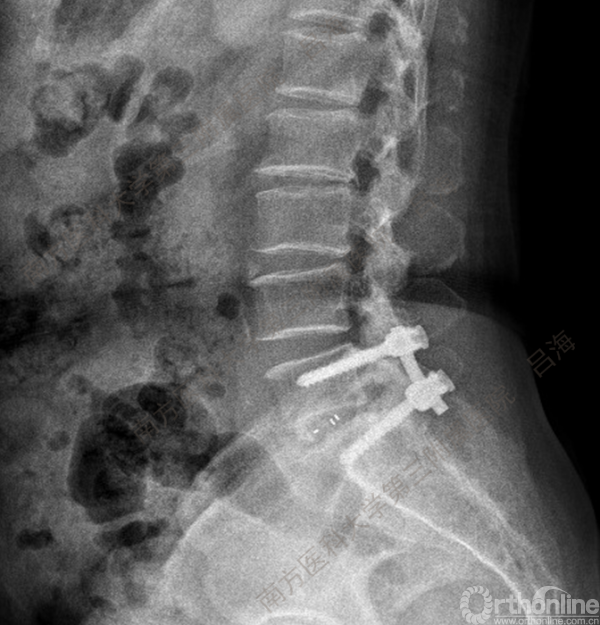

随着社会老龄化进程加快,胸腰椎退行性病变的治疗已经成为脊柱学术界的一个热点话题。MIS-TLIF手术可以治疗多种不同的胸腰椎退行性疾病,南方医科大学第三附属医院吕海教授结合病例为我们一一展示了该术式在治疗不同胸腰椎疾病时的具体手术过程。